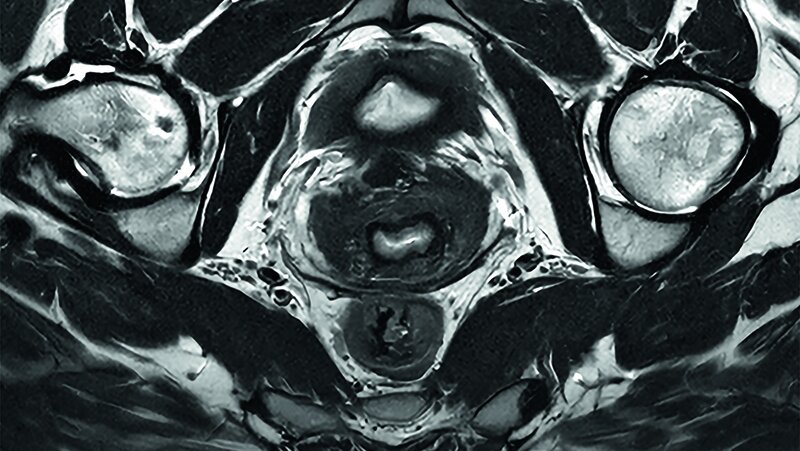

Diese Technologie der nächsten Generation erweitere die KI-gesteuerte Workflow-Effizienz und verbessere die Bildqualität im gesamten Philips BlueSeal MR-Portfolio, einschließlich bereits bestehender Systeme, betonte das Unternehmen. Auf dem ECR 2025 fand auch die europäische Premiere der neuesten Generation des 1.5T BlueSeal MR-Scanners mit komfortabler 70-cm-Öffnung im heliumfreien Betrieb statt. „Mit SmartSpeed auf unserem BlueSeal-Scanner haben wir die Untersuchungszeit für eine Ganzkörperuntersuchung von 75 auf 60 Minuten reduziert, sodass zwei Patienten mehr pro Tag gescannt werden können“, sagte Wayne Picker, Vizepräsident für klinische Technologie bei Prenuvo, Inc. Mit der neuesten Version der Bedienoberfläche – MR Workspace R12 – hat Philips einen „Zero-Click“-Workflow vorgestellt, der den gesamten Bildgebungsprozess von der Auswahl der Systemparameter bis zur Berichterstellung nahtlos steuern soll. Das Herzstück von SmartSpeed Precise ist die Anwendung zweier KI-Modelle in der Bilddatenrekonstruktion, die eine 80-prozentige Steigerung der Bildschärfe ermöglichen soll und die diagnostische Genauigkeit weiter verbessere. Zu den weiteren Innovationen gehöre Smart Reading, die erste und branchenführende Lösung, die eine cloudbasierte, KI-gestützte quantitative Berichterstattung integriere. Smart Reading nutze modernste KI-Plattformen wie icobrain (icometrix) für die Neurologie – einschließlich automatischer Erkennung der mit Alzheimer assoziierten Anomalien – und QP-Prostate (Quibim) für die fortgeschrittene Prostatakrebsdiagnostik.